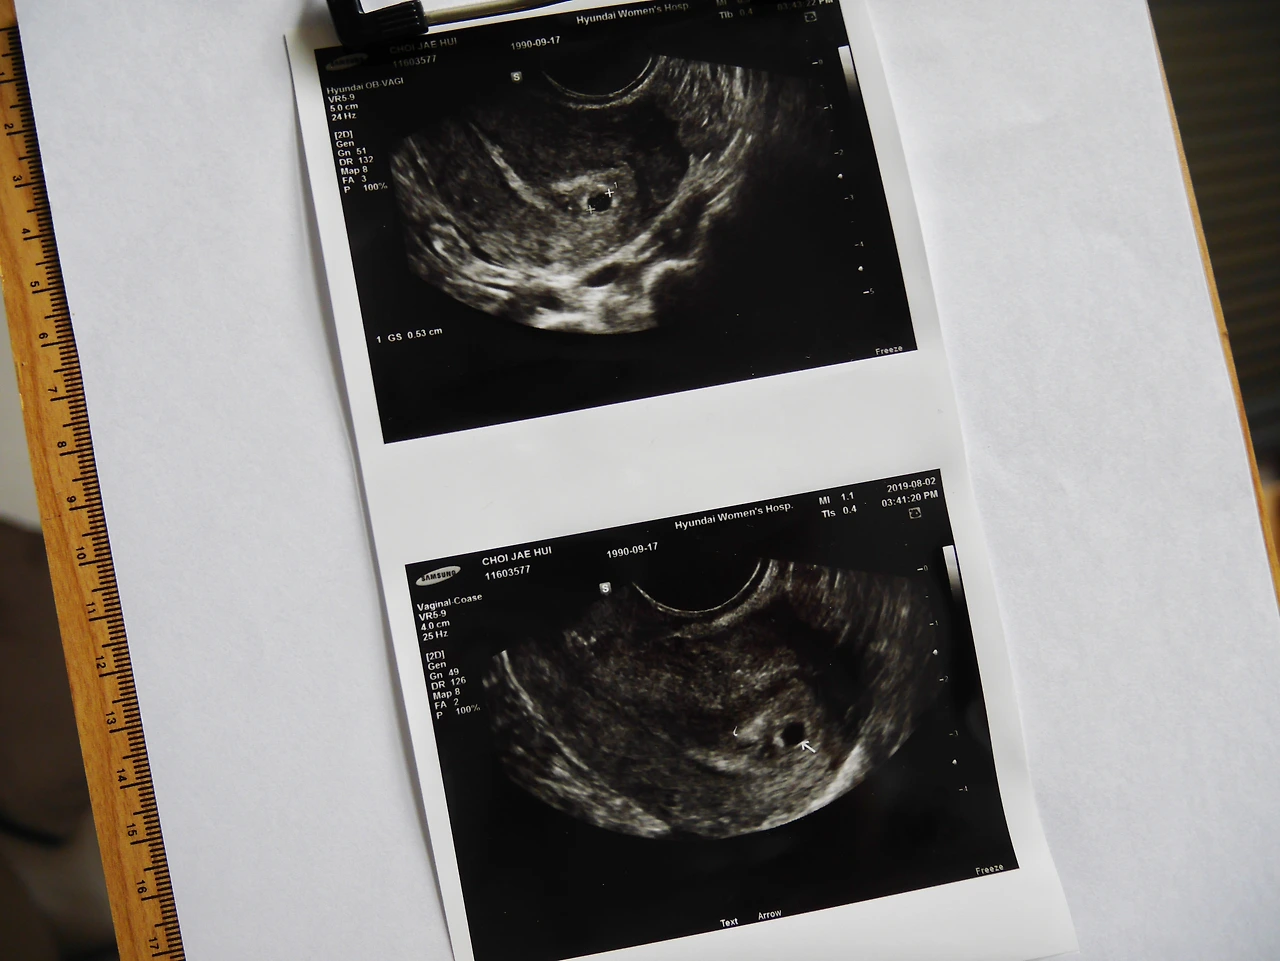

아기집 안 보이면 돈 내겠다는 맘으로 초음파를 했는데 다행히도 아기집이 보인다.

아기집은 5미리라 아직 몇 주 차인지 정확히 알 수는 없으나, 아기집이 보이니 현재 5주 차로 봐야 할 것 같다고 말씀하신다. 정확한 주수는 다음 방문 때 알려주신단다.

임신 시 주의사항이라던지, 앞으로 올 수 있는 증상이라던지, 아기집이 자리를 잘 잡았는지 등의 이야기는 안 해주고 자궁과 난소에 혹은 없고 오른쪽 난소에서 배란이 되었다고만 이야기해주셨다.

초음파 사진을 가족들에게 보내줬더니 시어머니께서 눈물이 날 것 같다고 전화하셨다. 양가의 첫아이라 모든 게 신기하고 감동적이다.

나의 출산예정일은 4월 9일. 그런데 아기집이 일찍 보이니 아마 4월 3일경으로 예정일이 변경될 것 같다고 하셨다. 임신확인서를 받았는데도 얼떨떨하다. 심장소리를 들으면 실감이 날까?